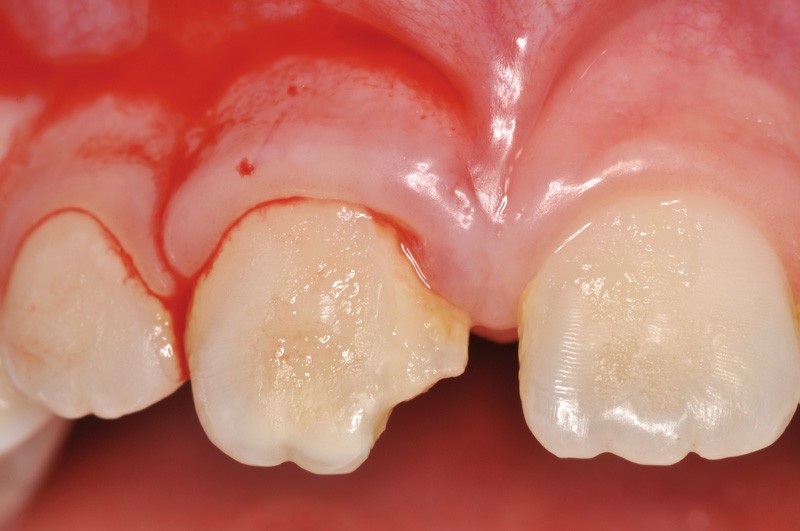

a à d Jeune patiente âgée de 8 ans, adressée suite à un traumatisme survenu 3 semaines auparavant, pour l’extraction de sa 21. La vue clinique montre un saignement ligamentaire, une mobilité coronaire et une fracture coronaire amélodentinaire longitudinale partant de l’angle mésial et se poursuivant en direction radiculaire sous-gingivale (a). Un test de vitalité positif indique que la dent est vitale, la radiographie permet de poser le diagnostic de fracture coronoradiculaire, et d’objectiver l’immaturité radiculaire (stade 8 de Nolla) (b). Une contention est mise en place et la plaie dentinaire coronaire est scellée au mieux par collage afin de limiter le risque d’une complication infectieuse (c). A 15 jours la dent est vivante et aucune complication n’est apparue (d). La patiente est revue après 3 mois pour déposer la contention, le test de vitalité est positif, et la radiographie de contrôle montre une apexogenèse en cours (e). Cependant la gencive s’est invaginée dans le trait de fracture (f). La zone est débridée sous microscope (g) puis scellée et reconstituée à l’aide d’un adhésif SAM et d’un composite fluide (h). Le contrôle radiographique à 6 mois est satisfaisant (i). Ce cas clinique illustre le fort potentiel des pulpes jeunes et du ligament alvéolodentaire à résister aux agressions et à assurer les fonctions dentinogénétiques et l’édification radiculaire.